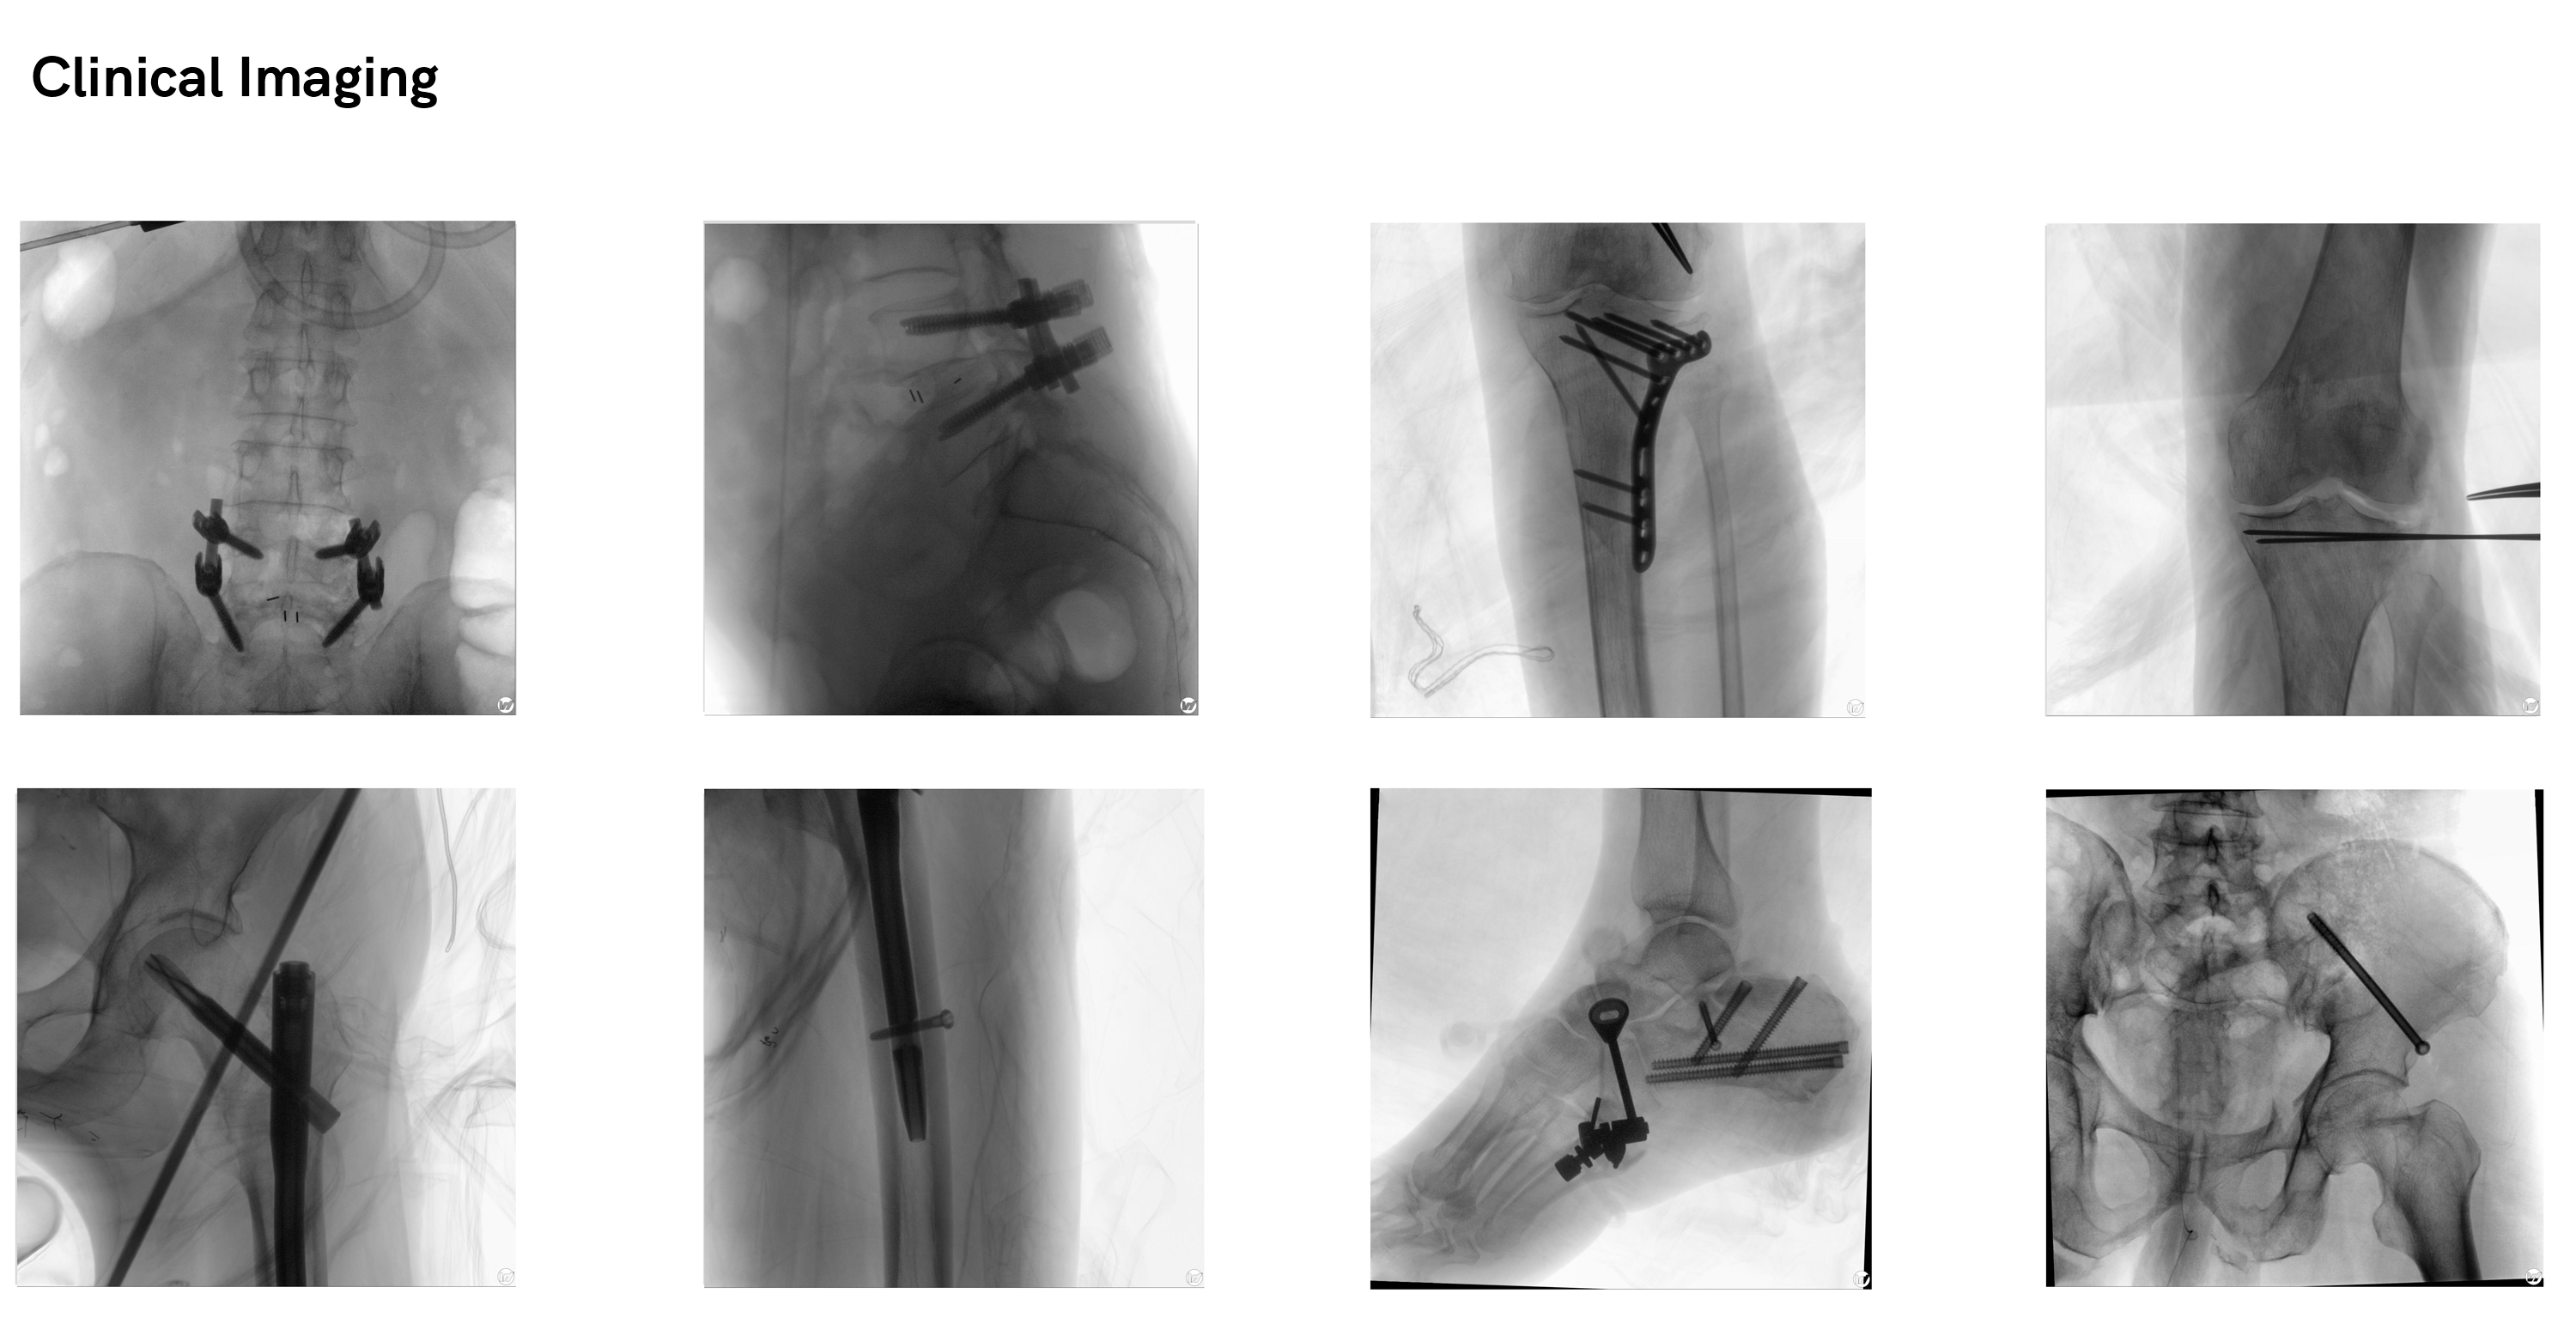

WIL Meta Attain® 3D C-arm

Clinical field

Orthopedic Spine

Orthopedic Trauma

Orthopedic Joint